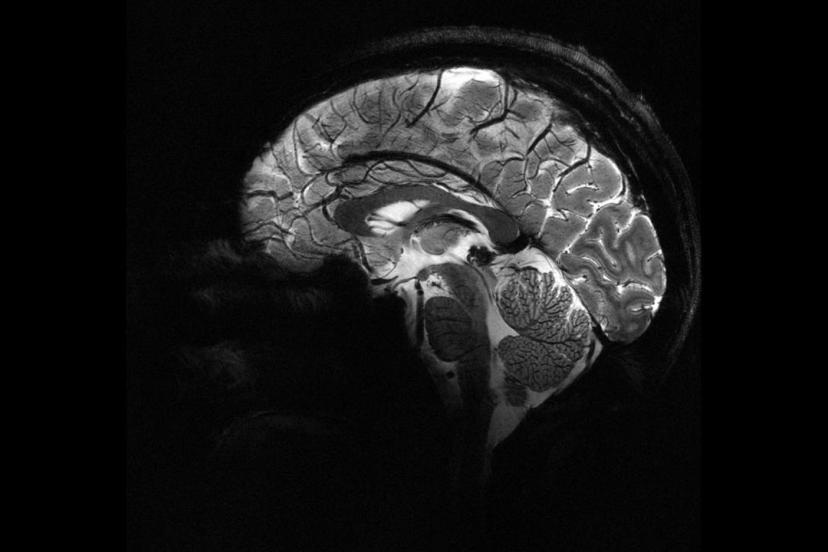

Beyne verilen elektrik akımı bencilliği azaltabilir mi?

Zürih Üniversitesi'nde yürütülen yeni bir araştırma, beynin iki farklı bölgesini uyararak, insanların daha az bencil olmalarını sağlamanın yolunu buldu.

Deney sırasında beynin ön ve arka kısımlarında yer alan frontal ve paryetal bölgelere elektrik akımı uygulandı. Bu iki bölge aynı anda uyarıldığında, katılımcıların daha fazla para paylaştığı gözlemlendi.

Bu çalışma, katılımcıların para paylaşma oyunu sırasında beyin aktivitelerinin izlendiği önceki bir araştırmaya dayanıyor. Önceki çalışmada, daha fazla para paylaşıldığında beynin karar verme ve empati bölgelerinin aynı frekansta "iletişim kurduğu" tespit edilmişti. Yeni deneyle birlikte, dışarıdan müdahale ile bu bölgeler arasındaki iletişimin tetiklenebileceği ve insanların daha özverili kararlara yönlendirilebileceği kanıtlanmış oldu.